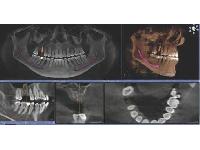

Where decades of experience meet the latest in technology, that's where you'll find Dynamic Dentistry provided by Dr. Rod Johnston! Serving the North Bay area for over twenty-five years, Dr. Johnston and his friendly team are passionate about giving you your best smile possible.

Passionate about his work, Dr. Johnston uses the latest technology to provide smile makeovers, and has changed many lives. Dr. Rod Johnston and